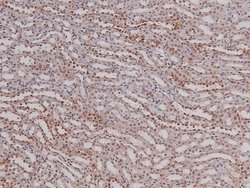

Phospho-p27 Kip1 (Thr157) Polyclonal Antibody for Western Blot, ICC/IF, IHC (P)

| Immunohistochemistry (Paraffin), Western Blot, Immunocytochemistry | |

| A synthesized peptide derived from human CDKN1B(Accession P46527), corresponding to amino acid residues around phosphorylated Thr157. | |